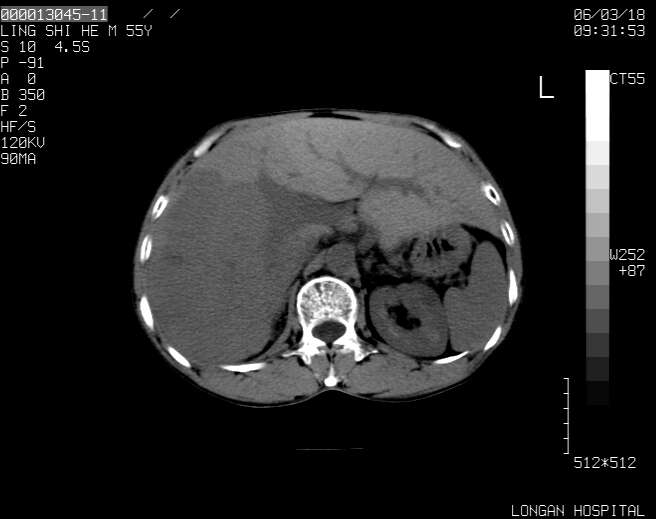

以下是引用guzhongliangddd在2006-3-21 22:13:00的发言:[br]病灶主要位于肝右叶的后份,内见异常血管,门脉主干及右支受侵{提示有癌栓形成},门腔间隙内见增大淋巴结。肝左叶内未见异常。

以下是引用zhuxinli在2006-3-22 1:23:00的发言:[br][br] 病灶主要位于肝右叶的后份,内见异常血管 .门脉右支截断,右叶前段早期强化(考虑动静脉漏),腹膜后肿大淋巴结,病灶逐渐强化,考虑为胆管细胞癌[br]